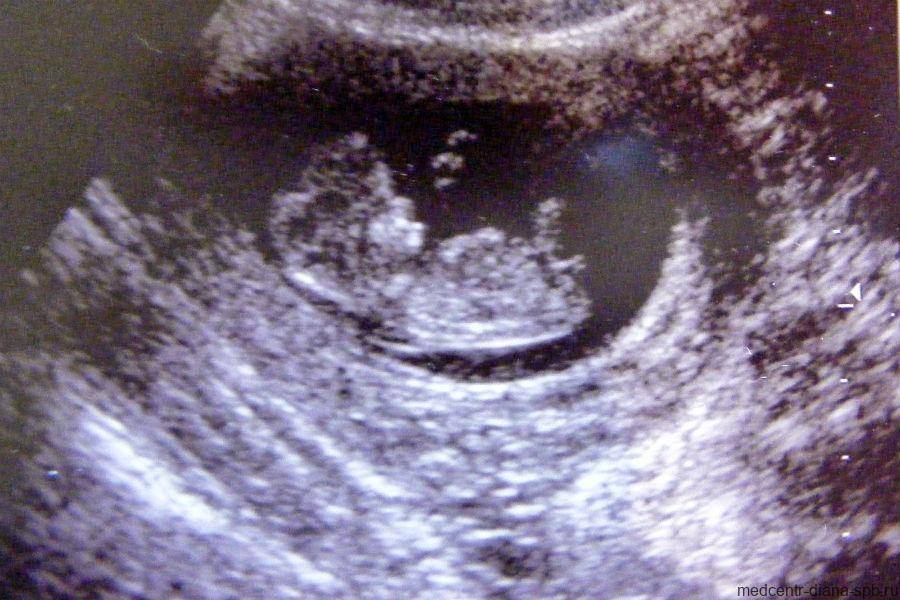

Фото УЗИ ребенка на 9 неделе беременности

В этот период происходит активное формирование структур мозга, в частности гипофиза и мозжечка. Нижние и верхние конечности удлиняются, у малыша появляются почки и печень. Также идет закладка черт лица. Пол ребенка еще не определяется, однако в организме плода начинают вырабатываться половые клетки – яйцеклетки у девочек и предшественники сперматозоидов у мальчиков. Размеры плода можно сравнить с размерами крупной вишни.

На УЗИ врач четко видит многоплодную беременность, а также определяет место прикрепления плодов. Сердцебиение хорошо прослушивается. На снимке не видны патологии и пол ребенка.